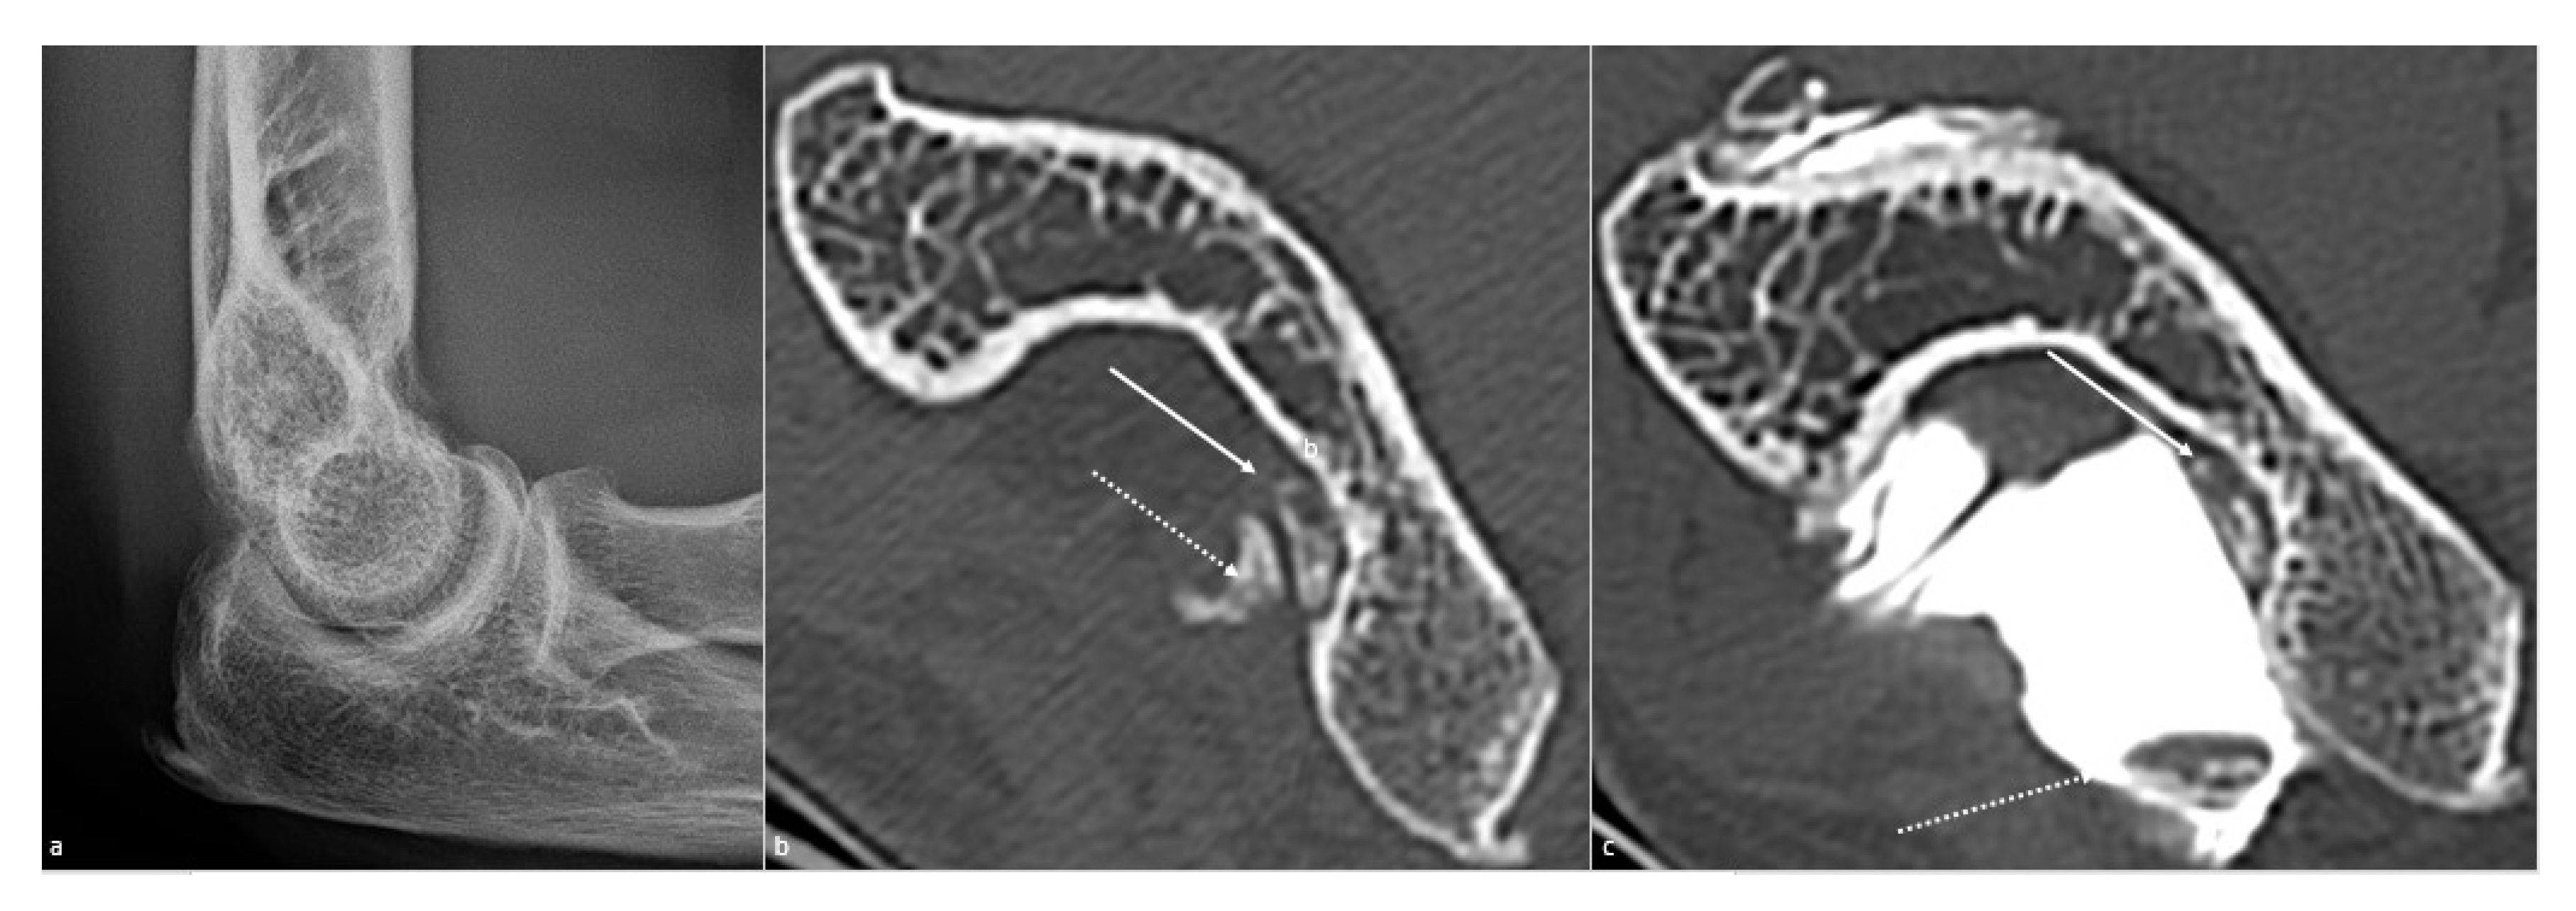

5.3. CT and CT Arthrography